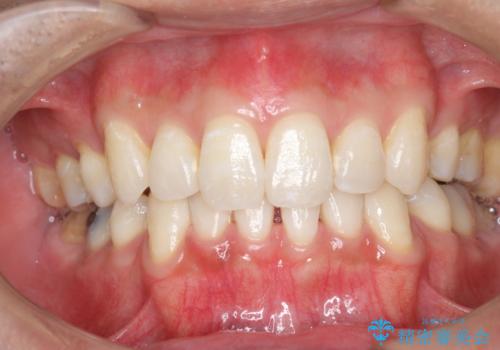

60分のPMTCで歯の黄ばみをきれいに除去

- 年末年始と忙しく、なかなか歯のケアがしっかりできなかった事と着色も気になるとのことで来院されました。PMTC60分コースを行いました。